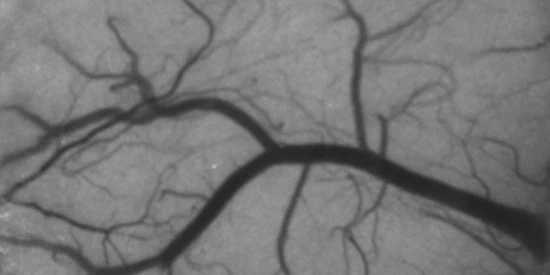

We develop blood flow imaging systems based on laser speckle contrast imaging (LSCI) to study the effects of ischemic stroke and to better understand the physics of dynamic light scattering.

We developed an advanced form of LSCI called multi-exposure speckle imaging (MESI) that offers more versatile and robust estimates of blood flow across a wider range of speeds.